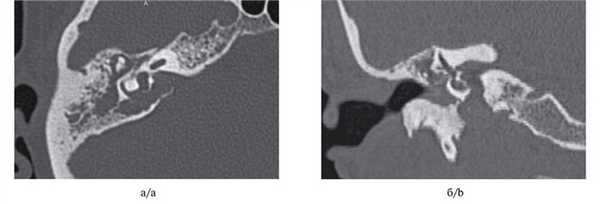

МСКТ височной кости — КТ-картина образования пирамиды правой височной кости с костно-деструктивными изменениями, правостороннего среднего отита. Образование на МСКТ височной кости отграничено сверху базальным завитком улитки и преддверием, снизу — яремной веной, медиально — твердой мозговой оболочкой задней черепной ямки, латерально — гипо- и мезотимпанумом, спереди — вертикальной частью внутренней сонной артерии, сзади — сагиттальным ПК, внутренним слуховым проходом (рис. 1). Рис. 1. МСКТ височной кости (правое ухо). КТ-картина инфралабиринтной холестеатомы пирамиды височной кости (а — аксиальная проекция, б — коронарная проекция).

МРТ среднего уха — в области нижней и задней граней пирамиды височной кости инфралабиринтно визуализируется образование размером 15,6×26×20 мм, прилежит и компримирует внутреннюю яремную вену, характеризуется преимущественно гиперинтенсивным сигналом в Т2, STIR, умеренно гиперинтенсивным в Т2 flair, изоинтенсивным в Т1 ВИ, с повышением сигнала на DWI с коэффициентом В 1000 и вычитанием на ИКД-картах, что соответствует холестеатомным массам.

Через 6 мес по результатам отомикроскопии, МСКТ височных костей, МРТ среднего уха в DWI-режиме: в сосцевидном отростке, в аттико-антральной области, в области нижней и задней граней пирамиды височной кости визуализируется обширная послеоперационная полость; в барабанном и мастоидальном сегментах послеоперационной полости пристеночно визуализируется содержимое умеренно неоднородной структуры, гетерогенного МР-сигнала в Т2 ВИ, STIR, T2 flair, изоинтенсивное в Т1 ВИ, без повышения сигнала на DWI c коэффициентом В 1000 и вычитанием на ИКД-картах (вероятно, рубцово-фиброзные изменения): данных за рецидив холестеатомы получено не было (рис. 4). Рис. 4. МР-томограмма среднего уха, выполненная в DWI- режиме.